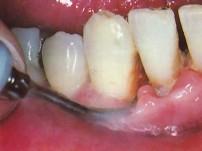

使用超声波洁牙机时,工作头应与牙面成()A.10度角左右B.15度角左右C.20度角左右D.25度角左右E.80度角左右

问题 使用超声波洁牙机时,工作头应与牙面成()

选项 A.10度角左右 B.15度角左右 C.20度角左右 D.25度角左右 E.80度角左右

答案 B